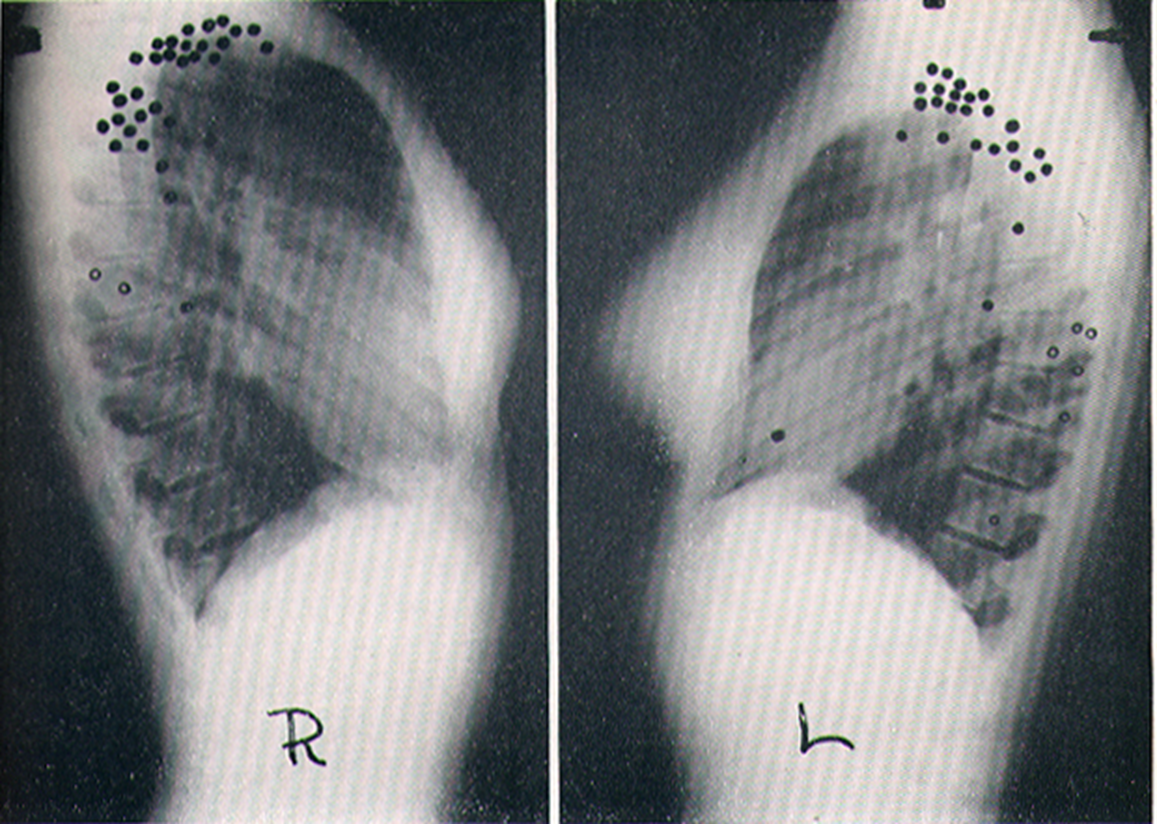

Location Of Primary Calcified Foci

primarily in lower lobesÂ

Location Of Re-Infection Tuberculosis

cluster in upper lobes

Location Of Single Tuberculosis Cavities

RML interestingly spared